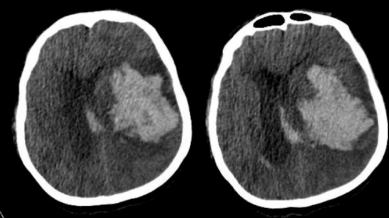

Paciente do sexo masculino, 72 anos, deu entrada no departamento de emergência com história de cefaleia súbita, evoluindo com vômitos e rebaixamento do nível de consciência. Antecedente de hipertensão arterial sistêmica e tabagismo, porém familiares não sabem referir nome das medicações em uso. Necessitou de intubação orotraqueal para proteção de vias aéreas. No momento, em ventilação mecânica modo assistido-controlado. Pressão arterial: 160x100mmHg. Frequência cardíaca de 78 batimentos por minuto. Anisocoria (midríase à esquerda). Exames laboratoriais evidenciaram: hemoglobina 13g/dL, leucócitos 13.000/mm3, plaquetas 220.000/mm3, ureia 60mg/dL, creatinina 1,6mg/dL, tempo de protrombina com INR (international normalized ratio) de 4,20, tempo de tromboplastina parcial ativado com relação P/N (paciente/normal) de 1. Tomografia de crânio sem contraste evidenciou o resultado a seguir. |

A terapia farmacológica indicada nesse momento é

Considerando as informações disponibilizadas, o diagnóstico provável é de